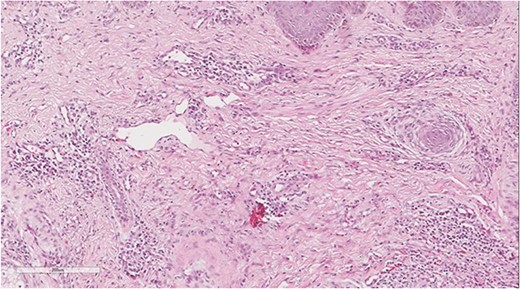

A 5 mm skin punch biopsy was also taken from the neck. Histopathology showed cystically dilated hair follicle with surrounding fibrosis and heavy inflammatory infiltrate and granulation tissue (Fig. 1), the inflammatory infiltrate is composed of lymphocytes, plasma cells, neutrophils and histiocytes (Fig. 2). The overall morphologic picture was suggestive of follicular occlusion syndrome (Fig. 3). A diagnosis of HS was made, and the patient was started on rifampin 600 mg OD and clindamycin 300 mg BID. A lipid panel was ordered as well and showed a triglyceride level of 1.99 mmol/L (0.7–1.7 mmol/L).